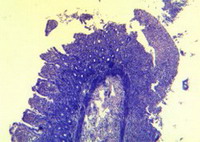

Միկրոցիրկուլյատոր հունի լայնացած անոթների (հիմնականում երակիկների) լուսանցքում PAS-ռեակցիայով հայտնաբերվում է էրիթրոցիտների ագրեգացիա՝հոմոգենացմամբ և հիալինային թրոմբոգոյացմամբ (նկ. 3), ինչը վկայում է խորըդիսցիրկուլյատոր փոփոխությունների, տեղային թրոմբոհեմոռագիկ համախտանիշիմասին:

Նկար 2. Լիբերկյունի կրիպտաները (դրանցից երկուսում նշմարվում են ֆուքսիֆիլգրանուլաներ, իսկ մյուսներում՝ ոչ): Պիկրո-Մալորի 200 | Նկար 3. Ենթալորձային շերտի լայնացած երակիկներ, որոնք պարունակում ենդրական հիալինային թրոմբեր: PAS-ռեակցիան լրացուցիչ Մայերիհեմատոքսիլինով ներկված: PAS |